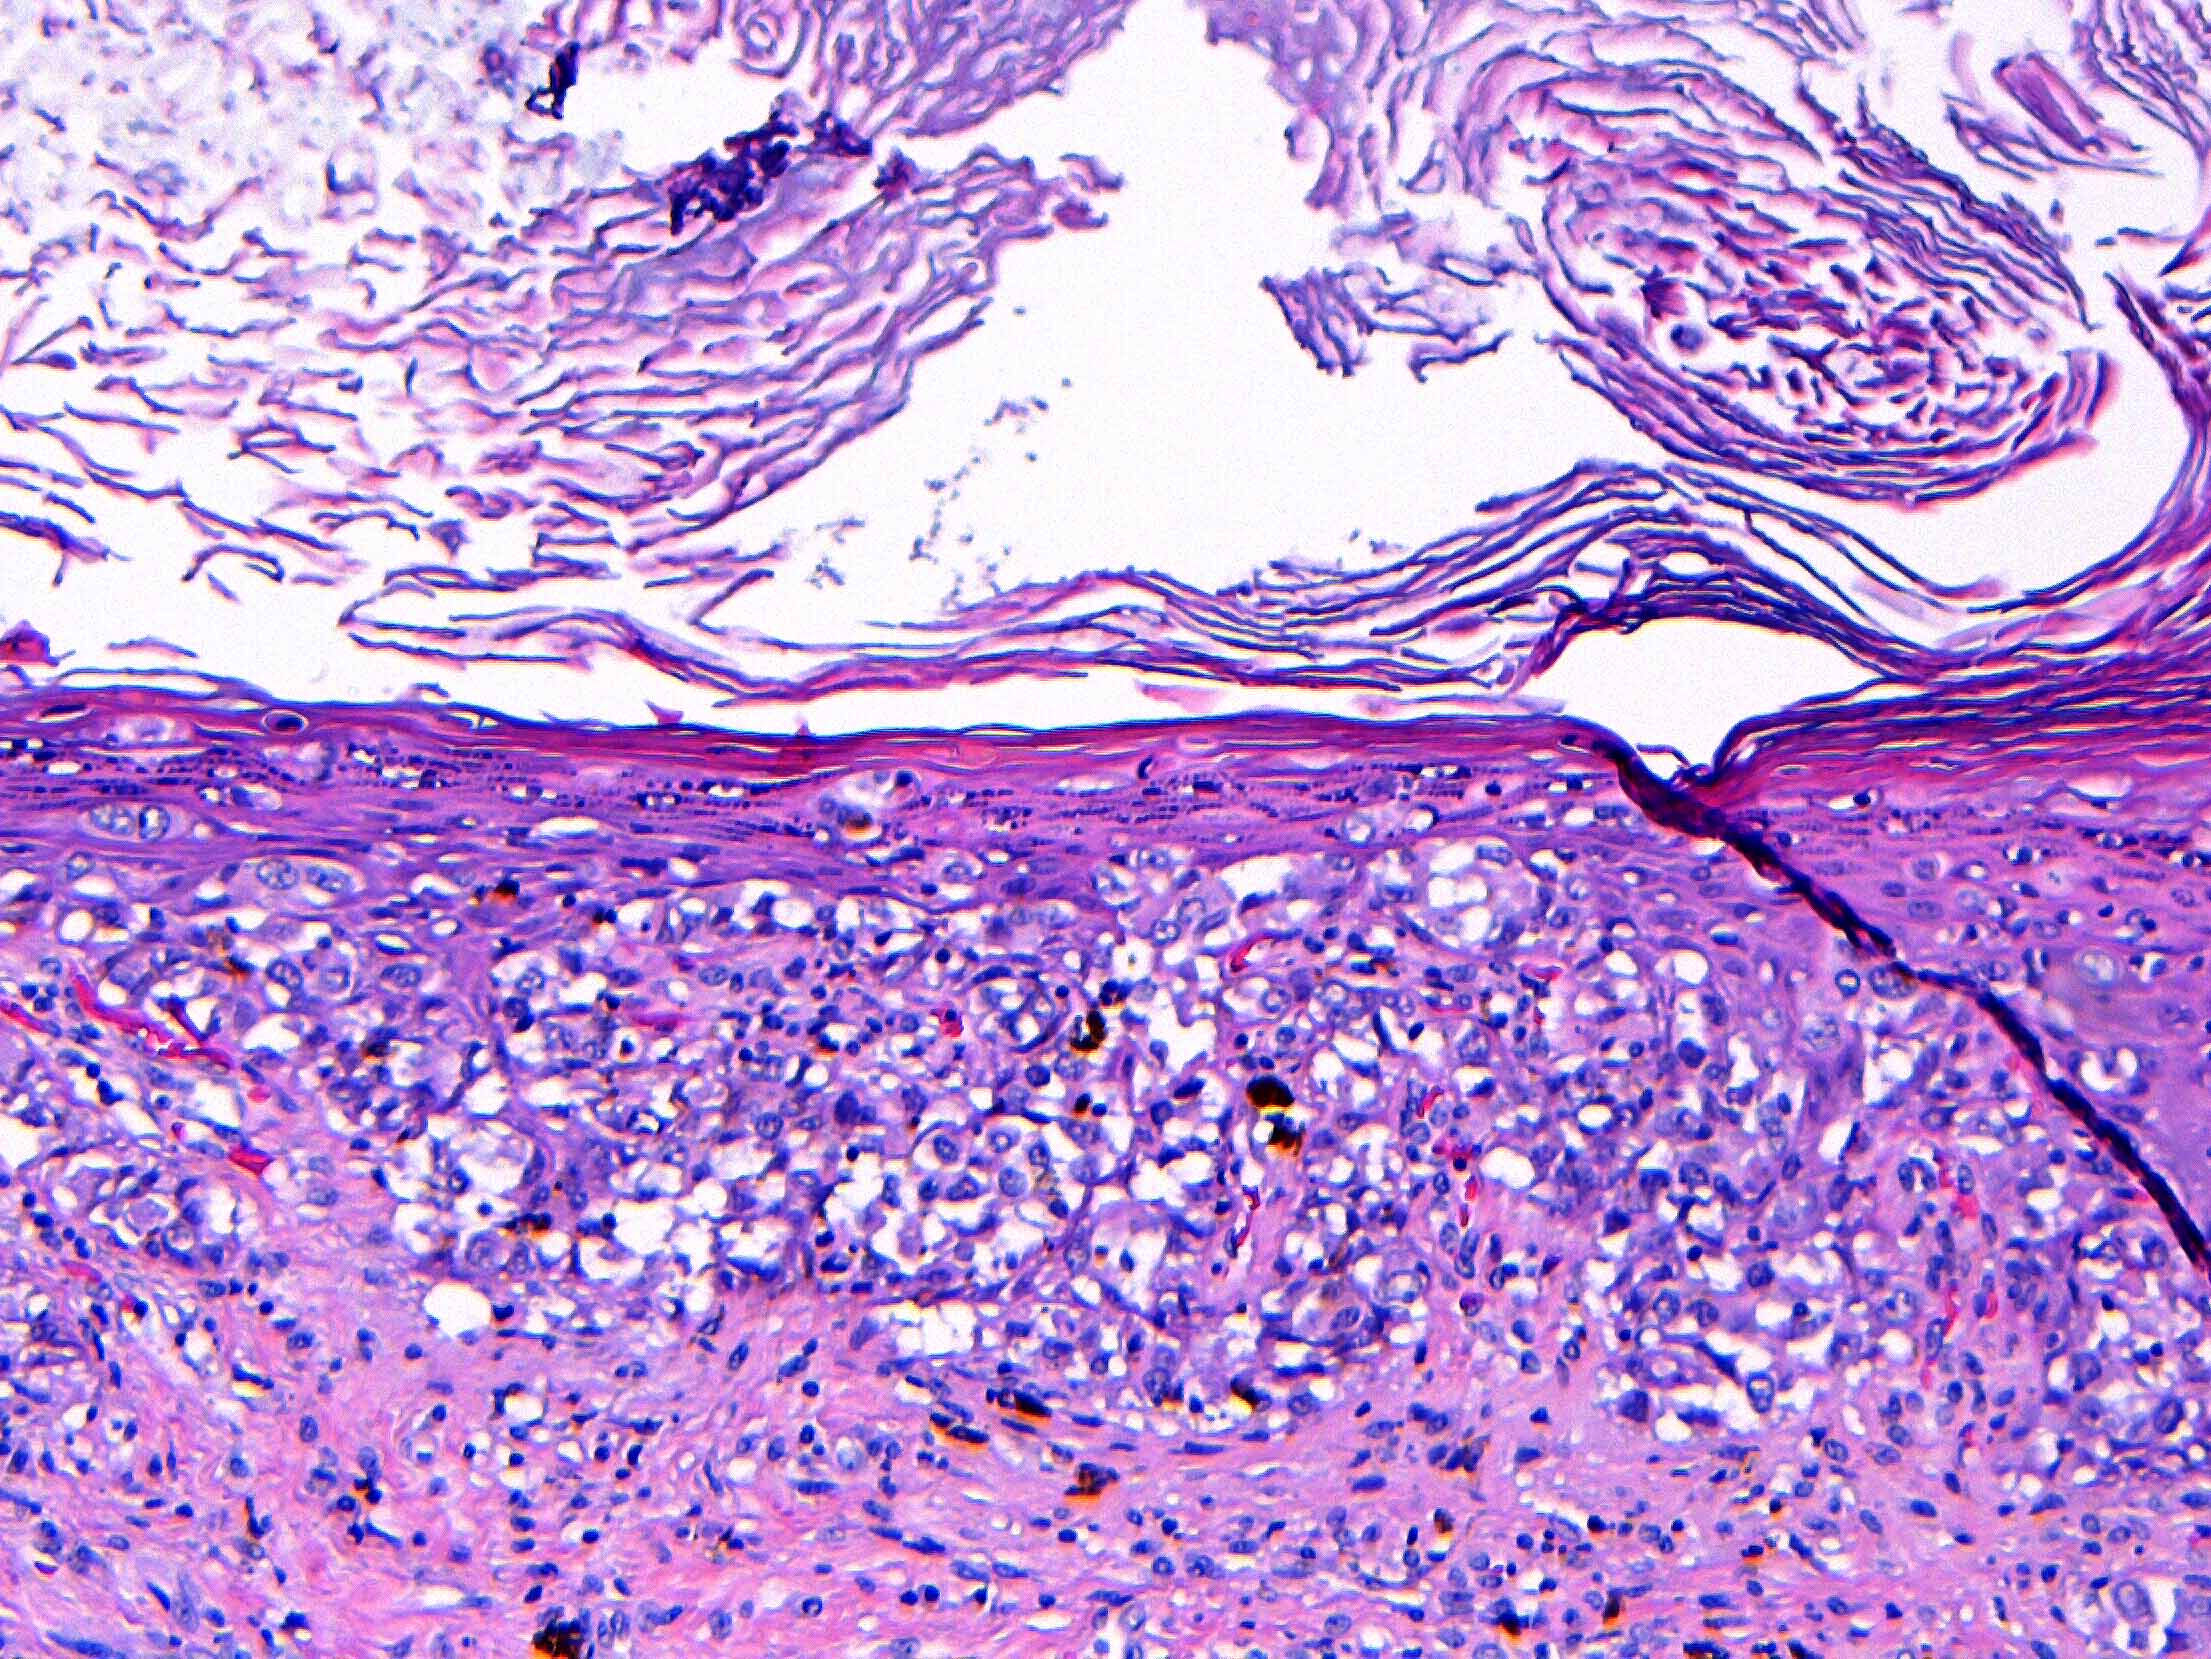

- Single cells or clusters of cells spread throughout the epidermis

- Cells have abundant pale cytoplasm, large irregular nuclei with prominent nucleoli

- Underlying dermis may have chronic inflammation

- Epidermis with hyperkeratosis and possibly ulceration

- Florid cases can show gland formation

- Paget cells may phagocytose melanin, mimicking melanocytes

- Underlying carcinoma is most commonly high grade invasive carcinoma of no special type (NST; 53 - 64%) or DCIS (24 - 43%) (Histopathology 2020;77:181)

Microscopic (histologic) images

Contributed by Anna Biernacka, M.D., Ph.D. and Mary Ann Gimenez Sanders, M.D, Ph.D.